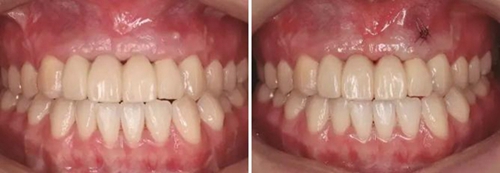

圖19 早期修復(fù)1月 圖20 早期修復(fù)2月

圖21 早期修復(fù)3月 圖22 早期修復(fù)3月打開三角間隙

圖23 早期修復(fù)4月 圖24 早期修復(fù)7月切除軟組織增生后

圖25 早期修復(fù)7月調(diào)改橋體部形態(tài)為卵圓形并高度拋光 圖26 早期修復(fù)8月

圖27 早期修復(fù)8月調(diào)改后 圖28 早期修復(fù)10月